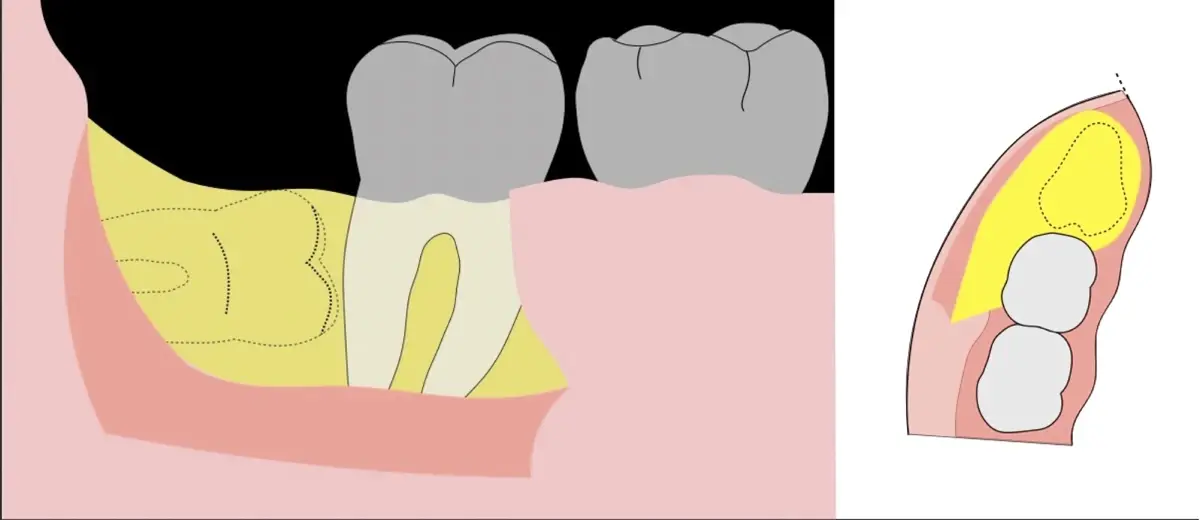

Es imprescindible conocer la ubicación de la tercera molar. Se puede emplear, adicionalmente a la evaluación clínica, herramientas radiográficas (panorámica y periapical) y tomográficas (Cone beam) para determinar la posición, grado de retención y proximidad a estructuras vecinas de riesgo como el nervio dentario inferior y así evitar lesiones (Figura 1).

Figura 1. Posición del tercera molar: Tercer molar en posición vertical (a). Tercer molar en posición mesioangulada (b). Tercer molar en posición horizontal (c).

El procedimiento se inicia colocando anestesia troncular para bloqueo del nervio dentario inferior y sus ramas. Luego, se establecerá el diseño de acceso según la disposición de la molar a extraer. Para fines didácticos, se explicará cómo se realizaría la extracción de la molar de la Figura 1: se realiza una incisión horizontal a nivel de la zona retromolar hasta llegar a distal de la segunda molar, continuándose con una incisión intrasurcular hasta mesial de la segunda molar, finalizando con una incisión vertical a espesor total hasta llegar a la línea mucogingival (Figura 2).